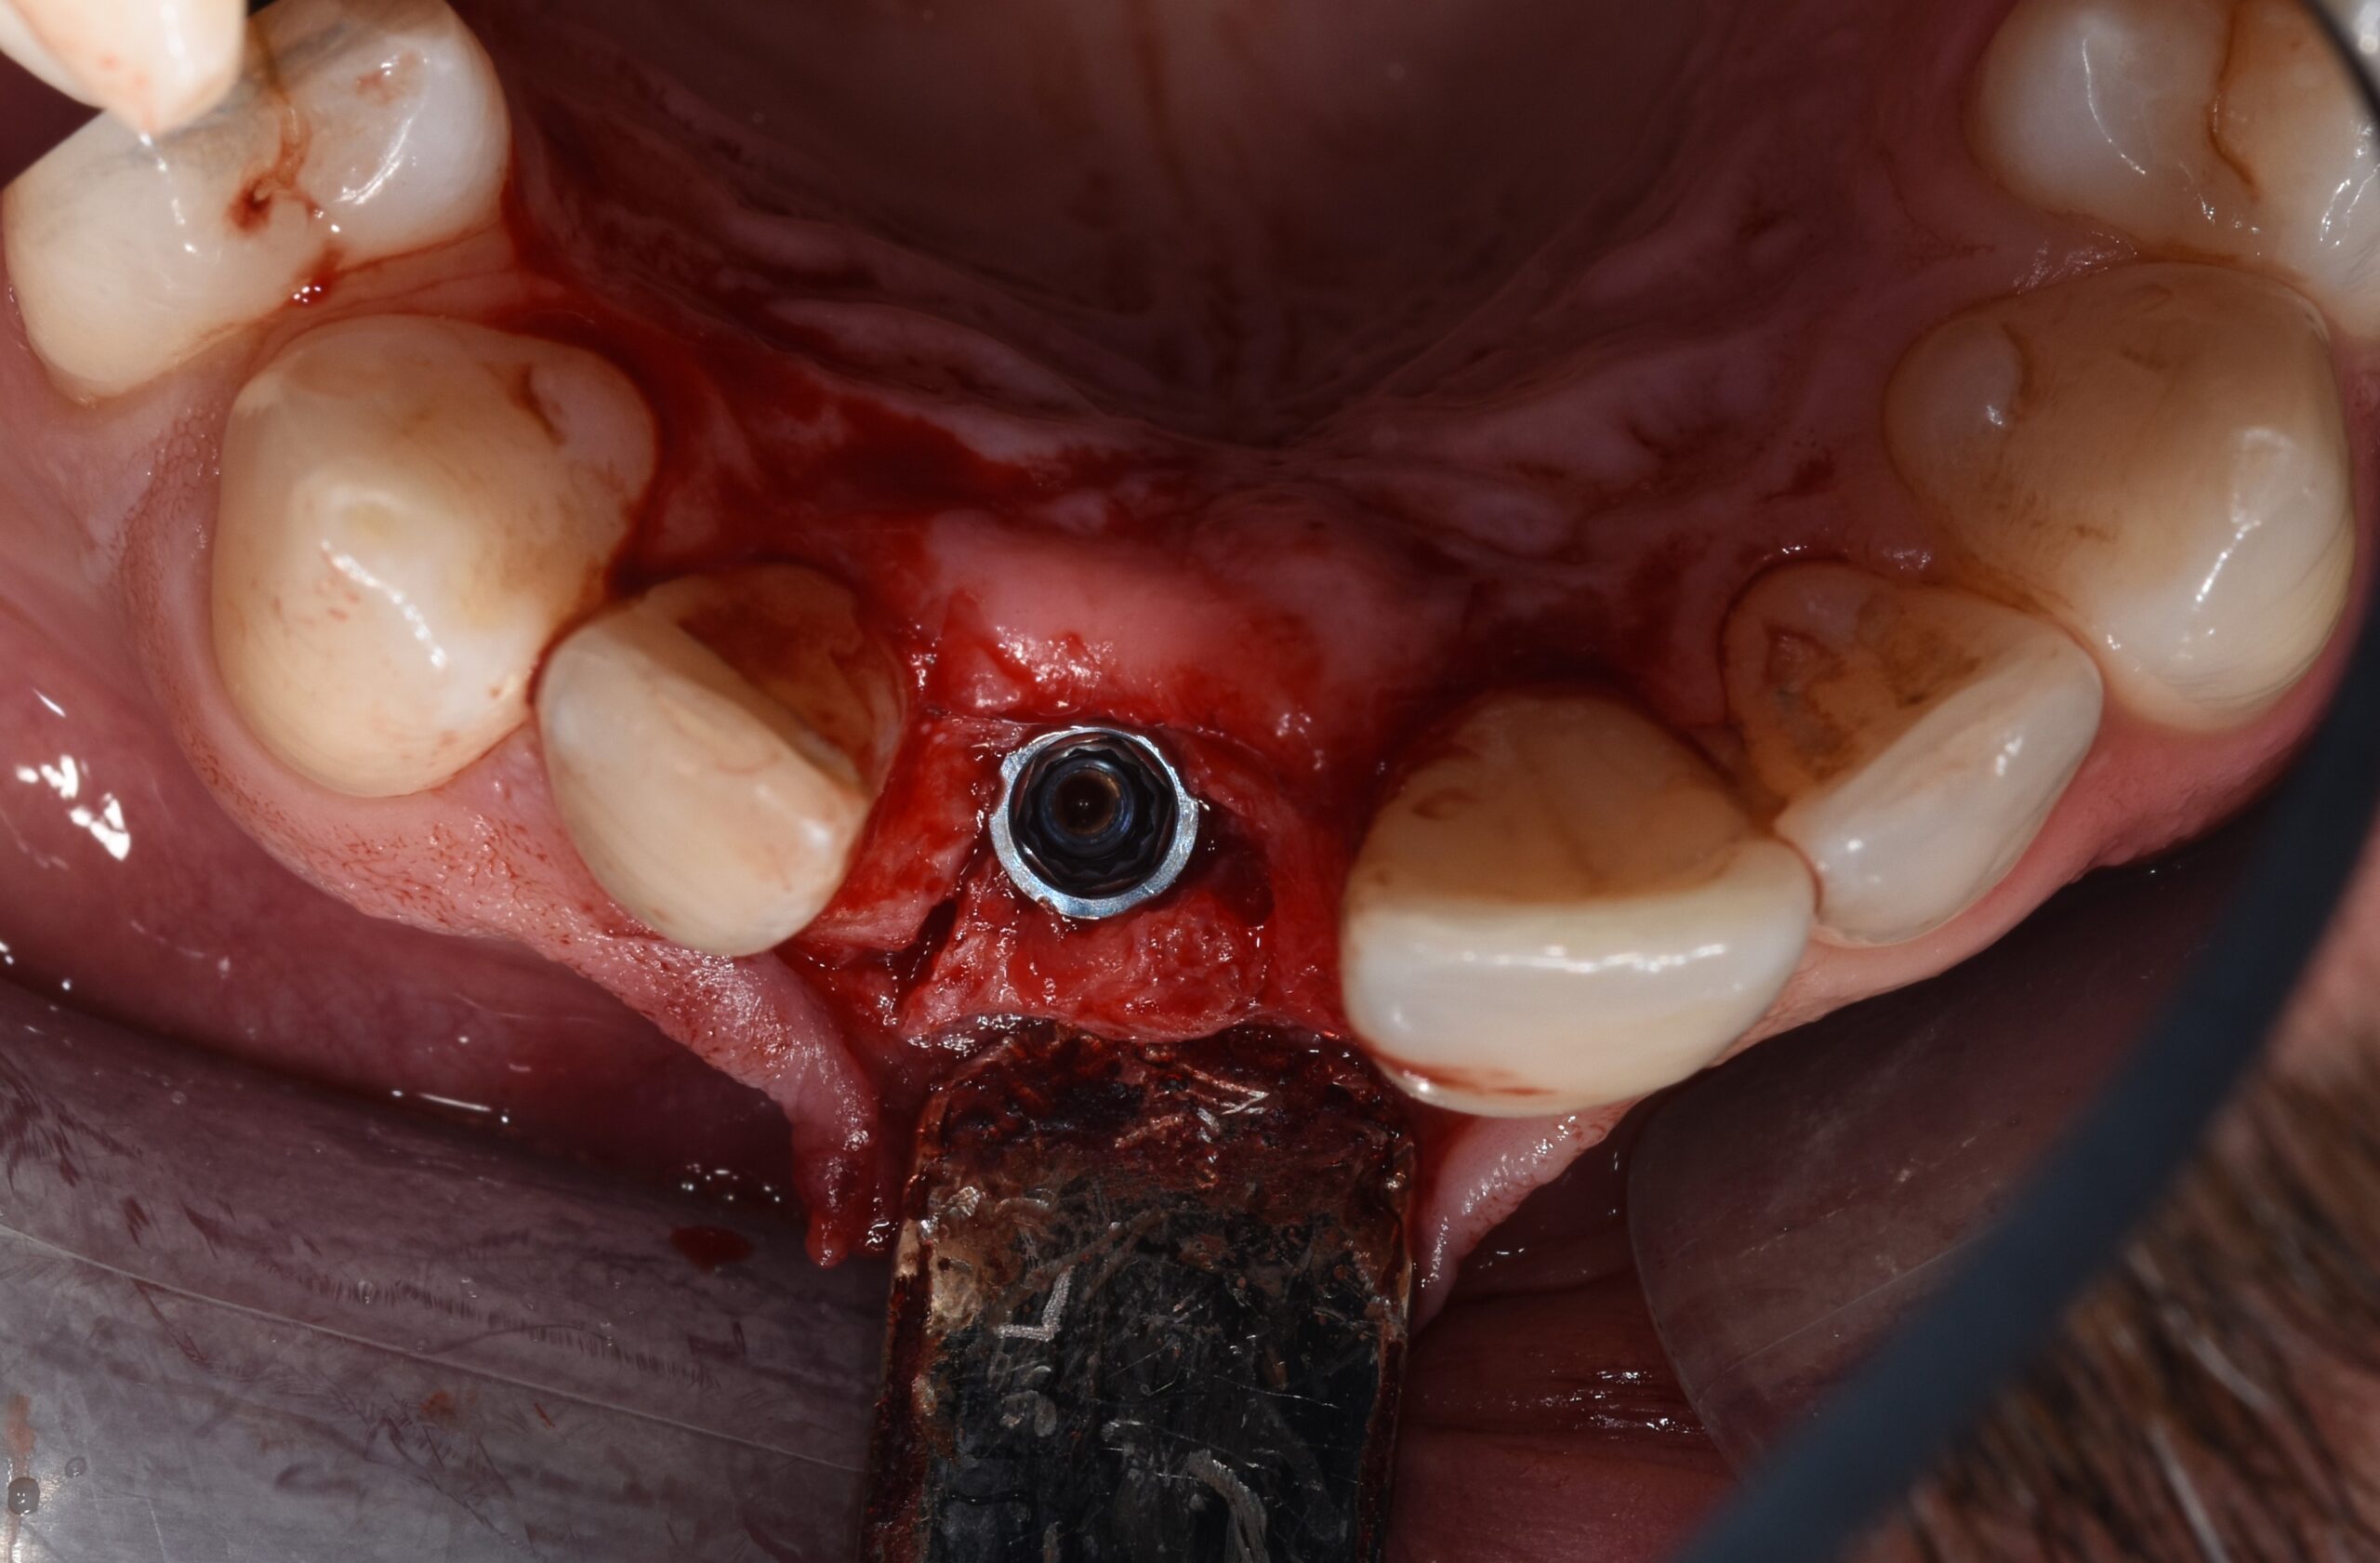

Sei mesi dopo, la verifica radiologica CBCT (Figura 7) evidenziava un recupero di radio densità (circa 400 HU) per cui veniva inserito un impianto Biomet-3I Osseotite Tapered Certain di 4 x 13 mm (Figura 8) con torque di inserimento di 20 Ncm.

La tecnica di espansione della cresta ossea (Figure 9-10) veniva scelta per l’osteotomia, con l’intento di compensare una inevitabile contrazione del suo spessore.